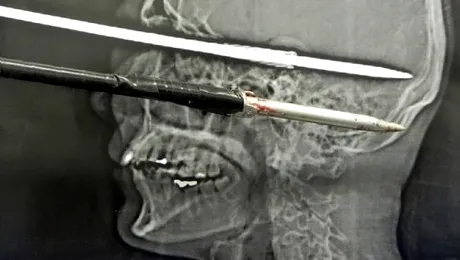

A supraviețuit după ce și-a înfipt accidental o săgeată în cap

Un adolescent a supravietuit dupa ce o sabie i-a strapuns craniul